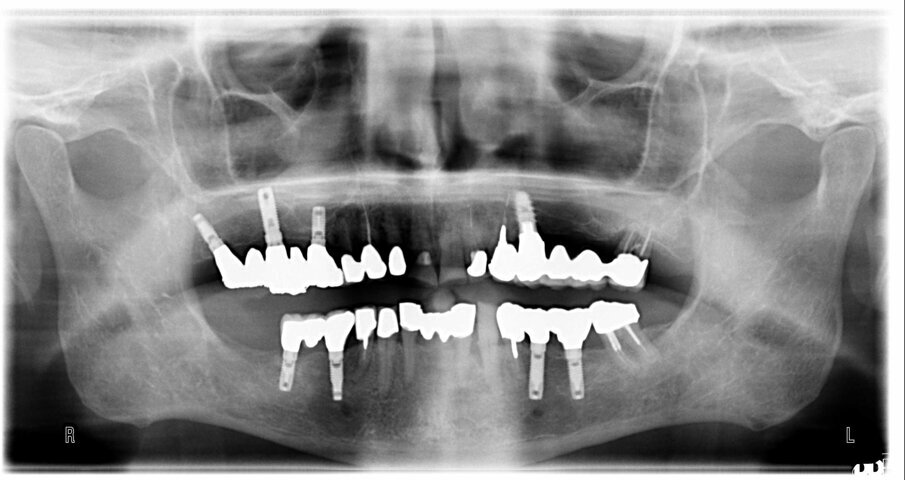

Le foto esplicative si riferiscono a un caso di riabilitazione estetica su paziente maschio di anni 76 con storia di bruxismo, in cui è stato inserito con carico immediato un impianto post estrattivo su 2.2 con mantenimento parziale del tavolato vestibolare nel rispetto del concetto di tunnel protesico di inserzione (Fig. 1). Il collare in zirconia è stato inserito per 1 mm sotto il tavolato e la porzione emergente ha la funzione di mantenimento a balcone del bombè connettivale e quindi di sostegno per i tessuti molli (Figg. 2, 3). La protesizzazione, avvenuta nelle 72 ore successive all’inserimento della fixture, è stata effettuata con impronta pick up e tecnica cementata con corona in PMMA eseguita al cad cam; l’angolo incisale della corona risultava assai smusso distalmente per agevolare i movimenti di svincolo in lateralità poiché il paziente è bruxista, come si evince dalle faccette di usura degli elementi naturali adiacenti (Fig. 4). Nonostante il biotipo gengivale sottile già nelle prime fasi dal carico si può notare l’effetto biomimetico del collare in zirconia e l’accettazione paraimplantare sul versante estetico.

È possibile affermare che l’impiego di impianti ibridi, dotati di collare in zirconia, costituisce oggi una scelta d’elezione per le riabilitazioni implanto-protesiche delle regioni estetiche, dove maggiore è l’aspettativa del paziente e dove maggiori possono essere le complicazioni di tipo non strettamente chirurgico. Questi impianti, infatti, sulla base delle nostre evidenze cliniche, si sono dimostrati straordinariamente performanti nella gestione dei tessuti molli e segnatamente nel mantenimento del trofismo connettivale, oltre che un eccellente baluardo nella riduzione della carica batterica peri-implantare.